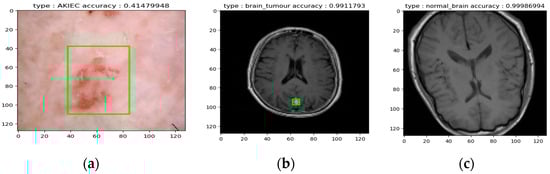

5.5. Evaluation of the Inception Model for Cancer Classification and Localization

- Image Acquisition: Single test images were presented to the model.

- Image Processing: The fine-tuned Inception model performed the following actions on each image:

- Classification: The model classified the image into one of ten categories:

- Seven classes of Skin Cancer: If a cancerous lesion was identified (e.g., potentially AKIEC skin cancer, as suggested in Figure 16a), the model attempted to classify the specific cancer type.

- Undefined Image: Images falling outside the expected range for skin or brain tissue were classified as “undefined.”

- Localization (if applicable): For classified skin or brain cancer images (as exemplified in Figure 16a,b), the model aimed to localize the potential lesion within the image.